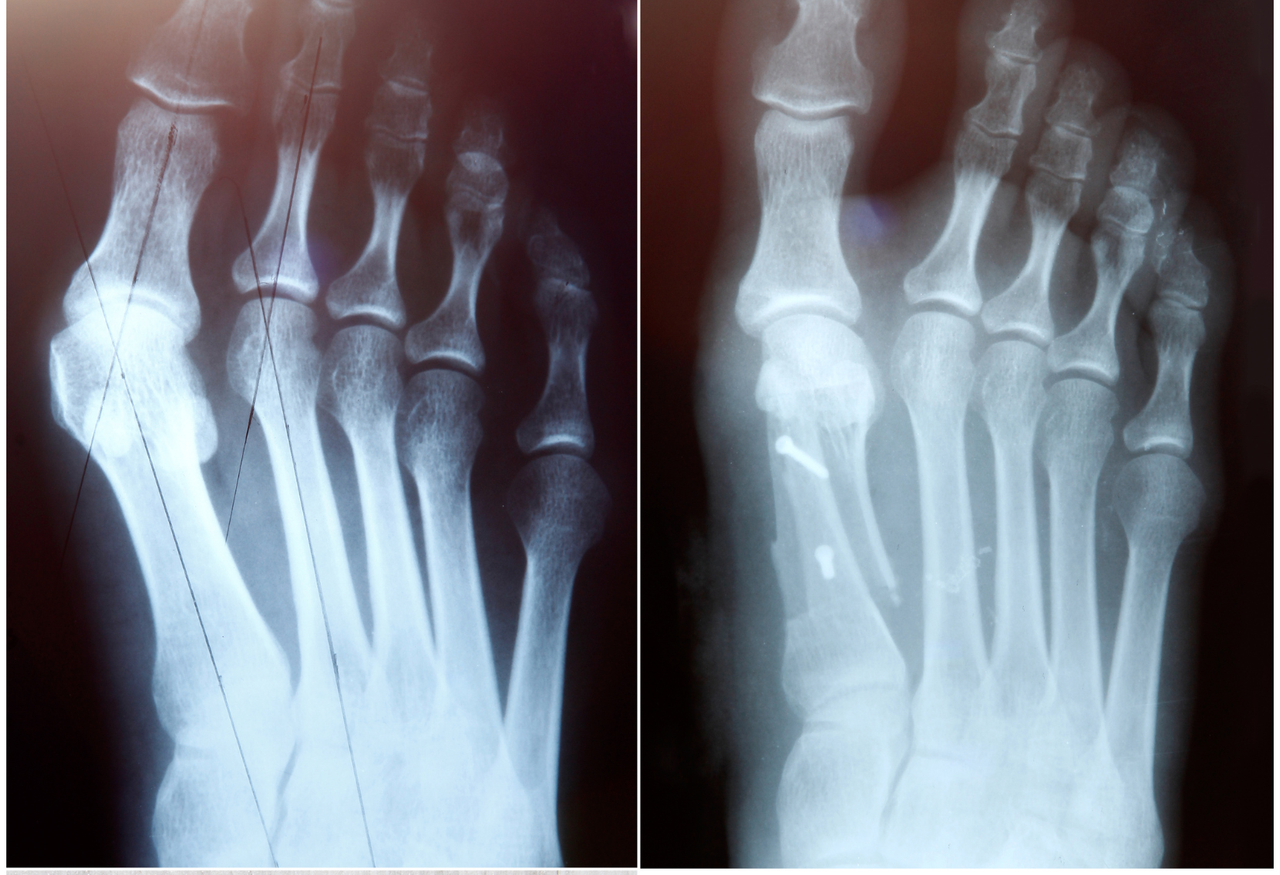

Pie_plano_y_alteraciones_de_la_pisada

Pie plano y alteraciones de la pisada

Diagnóstico y tratamiento de problemas en la estructura y apoyo del pie.